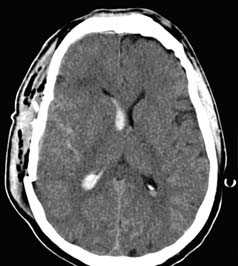

Применение компьютерной томографии в нейротравматологии существенно изменило представление о возможностях диагностики различных черепно-мозговых повреждений. КТ является в настоящий момент «золотым стандартом» - наиболее информативным методом обследования больных с черепно-мозговыми травмами и позволяет в самые короткие сроки судить о механизмах возникновения поражения мозга, его характере, распространенности, выраженности отека и дислокации мозга, а также динамике этих изменений.

- выявить наличие внутричерепной гематомы (её характер, локализацию, размеры),

- выявить наличие очага ушиба головного мозга (его локализацию, размеры, характер, наличие геморрагического компонента),

- выявить субарахноидальное кровоизлияние,

КТ с внутривенным контрастированием (КТ-ангиография) по неотложным показаниям, как правило, не выполняется. Показанием к такому исследованию является обнаружение на нативных томограммых внутримозговых гематом, локализующихся в местах возможного разрыва аневнизмы.